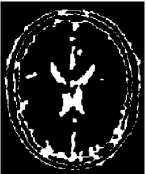

4.2 Inhomogeneous image segmentation

In this subsection, we extend our proposed method to segment two classes of inhomogeneous images shown in Figure 4.6. The left is a synthesized image by combining the arterial blood vessels of a human head. The right is a MRI brain image based on an anatomical model of normal brain from the slice 91 of the normal brain database, which is available to the public at http://www.bic.mni.mcgill.ca/brainweb/. Here we set as “modality=T1, Slice thickness=1mm, intensity non-uniformity = 20%” for the original image 4.6(b). Different to the numerical comparisons of the piecewise constant image, we do not know the real segmentation due to the inhomogeneity. So we except to obtain a better restored image as the stopping condition in the first step of our proposed strategy.

Refer to caption

(a) Synthesis Image

(b) MRI Image

Figure 4.6: The original images in Example 4.3 and 4.4.